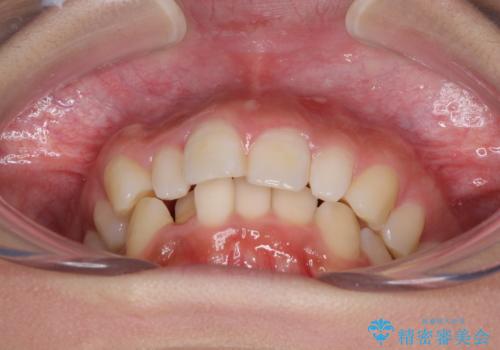

前歯のデコボコを治したい インビザラインによる矯正治療

- 前歯のデコボコ気になるとのことで来院された患者様です。

上下顎ともに歯列全体の後方移動とIPR(歯と歯の間を削る)によってデコボコが解消するように設計し、インビザラインにより治療を行うこととしました。